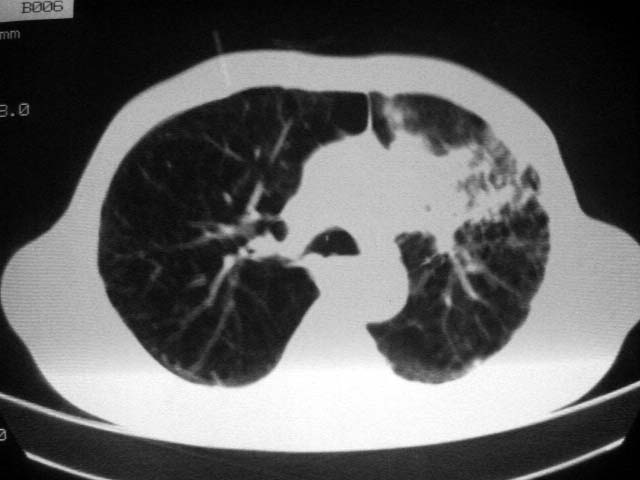

以下是引用zjzjr在2007-9-4 17:00:00的发言:[br]双上肺继发型结核伴左上肺空洞形成.慢性支气管炎伴肺气肿.

以下是引用liuzheng_9326在2007-9-4 16:23:00的发言:[br]痰检未见结核菌, 治疗后症状好转。图像符合陈旧性结核伴感染。